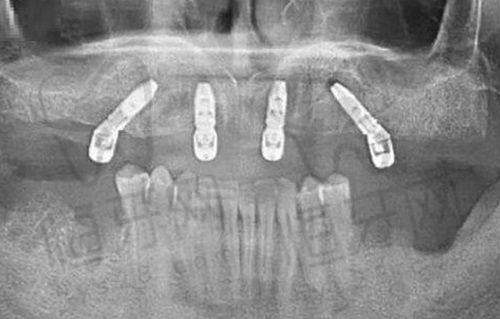

牙齿种植中 心:对于缺失牙齿的患者来说,牙齿种植是一个良好的解决方案。芜湖德瓦口腔门诊部的牙齿种植技术非常成熟,能够根据患者的具体情况选择合适的种植体,让种植后的牙齿更加稳固、美观,修复正常的咀嚼功能。

精良的设备和技术:门诊部引进了德国、瑞士等国内外精良设备,采用数字化诊疗技术。这些精良的设备和技术能够提高诊断的正确性和治疗的成效。例如,数字化口腔扫描设备可以快速、正确地获取患者口腔的三维数据,为医生制定治疗方案提供更严谨的依据。

门诊部引进了德国、瑞士等国内外精良设备。比如口腔CT设备,它可以提供口腔内部的三维图像,让医生更清晰地了解患者牙齿和颌骨的结构,对于牙齿种植、正畸矫正等治疗具有重要的指导意义。还有数字化口内扫描仪,它能够快速、正确地获取患者口腔的内部信息,避免了传统取模的不适感。此外,精良的消毒设备可以确保医疗器械的完全消毒,保护患者的安心。